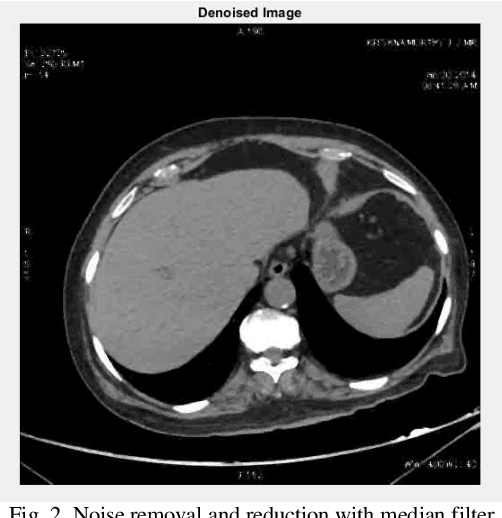

Abstract:Lung cancer is one of the prevalence diseases in the world which cause many deaths. Detecting early stages of lung cancer is so necessary. So, modeling and simulating some intelligent medical systems is an essential which can help specialist to accurately determine and diagnose the disease. So this paper contributes a new lung cancer detection model in CT images which use machine learning methods. There are three steps in this model: noise reduction (pre-processing), segmentation (middle-processing) and optimize segmentation for detect exact are of nodules. This article use some filters for noise reduction and then use Independent Recurrent Neural Networks (IndRNN) as deep learning methods for segmentation which optimize and tune by Genetic Algorithm. The results represented that the proposed method can detect exact area of nodules in CT images.